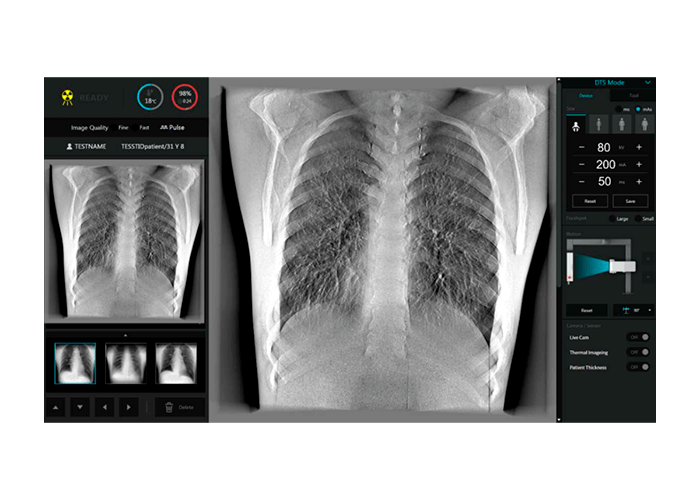

Interfase Digital

- Pantalla Infográfica

ExamVue DTS Suite

El software exclusivo para StriXion™ combina imágenes de rayos X en tiempo real (fluoroscópicas), rayos X convencionales y tomografía en una única solución. Utilizando la misma plataforma intuitiva y avanzada de ExamVue™ Duo, el software de StriXion™ permite un control completo sobre la adquisición de imágenes, la técnica utilizada y el proceso de diagnóstico.